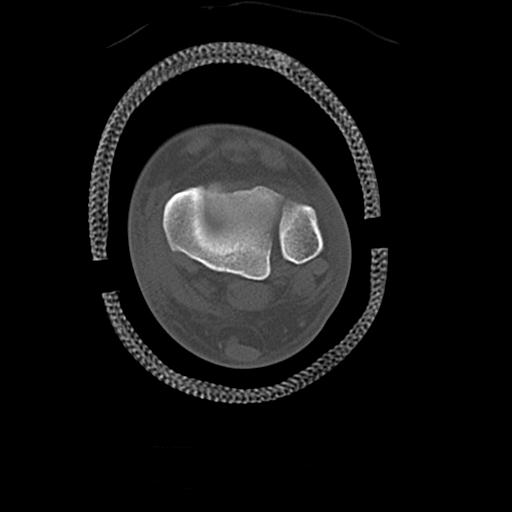

56476 8/28 4R 1/21 2R 左足関節 デジカメ写真 72歳女性 右足関節AS